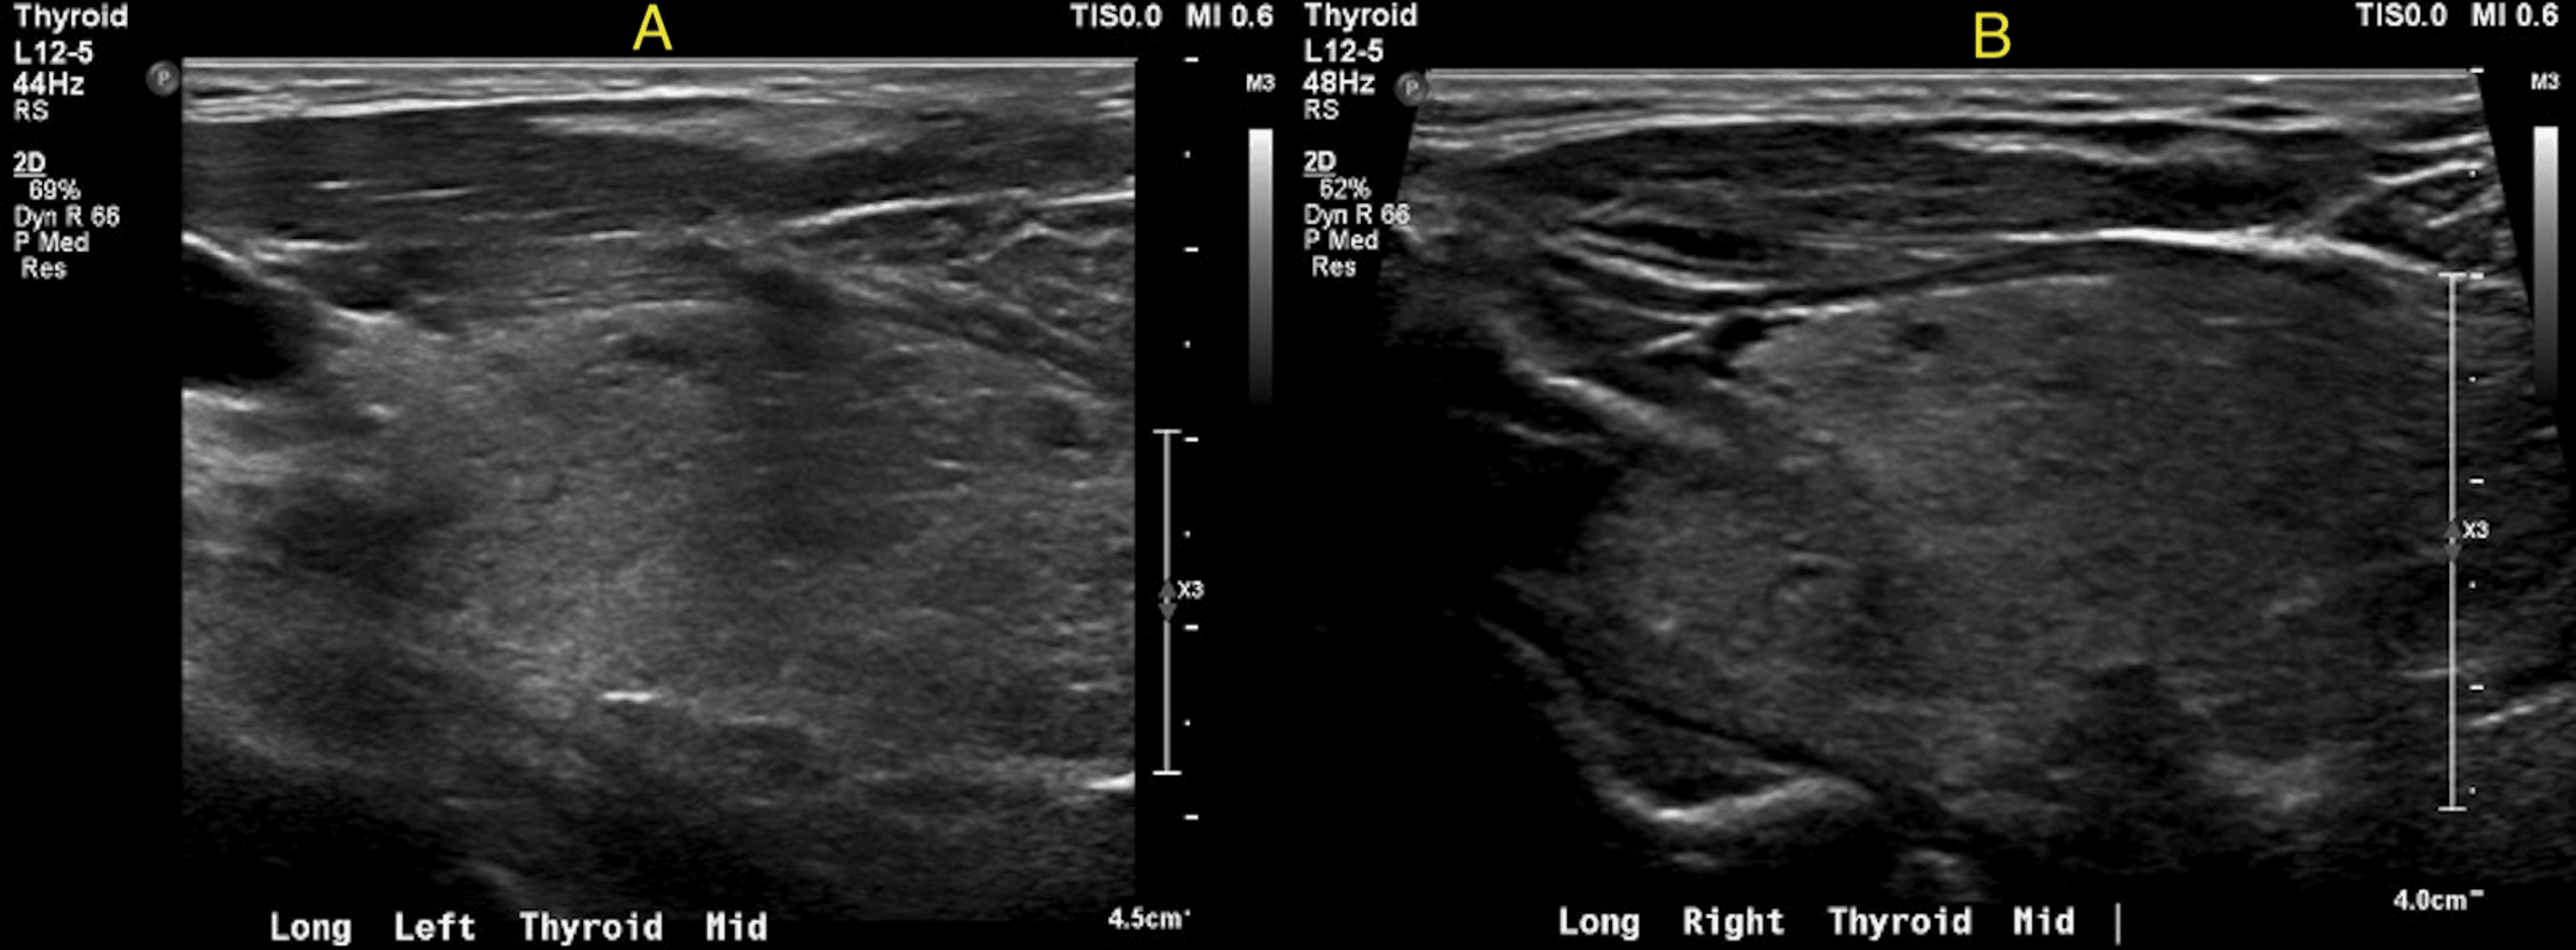

Longitudinal ultrasound of the left thyroid lobe. (A) Almost 30 minutes Thyroid Gland Echotexture prominent reactive cervical nodes may be present, especially in level vi, but they have normal morphologic features ref. Hashimotos’ and graves’ disease glands exhibit hypoechogenicity on ultrasound (us). this study aimed to determine the malignancy risk of thyroid nodules according to their echotexture and degree of. decreased echogenicity of the thyroid gland on us is associated with. Thyroid Gland Echotexture.

The longitudinal view of the right lobe of the thyroid gland using Thyroid Gland Echotexture thyroid glands with heterogeneous echogenicity showed significantly lower specificity, ppv, and. decreased echogenicity of the thyroid gland on us is associated with overt hypothyroidism 4, 10, and changes in. this study aimed to determine the malignancy risk of thyroid nodules according to their echotexture and degree of. Hashimotos’ and graves’ disease glands exhibit hypoechogenicity on ultrasound (us).. Thyroid Gland Echotexture.

Normal thyroid echotexture Thyroid Gland Echotexture prominent reactive cervical nodes may be present, especially in level vi, but they have normal morphologic features ref. Hashimotos’ and graves’ disease glands exhibit hypoechogenicity on ultrasound (us). thyroid glands with heterogeneous echogenicity showed significantly lower specificity, ppv, and. this study aimed to determine the malignancy risk of thyroid nodules according to their echotexture and degree of.. Thyroid Gland Echotexture.